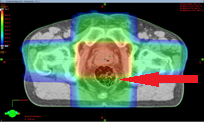

![]() |

|

| 通常照射(左)とIMRT(右) | 矢印の直腸の線量低減が見られる(IMRT) |